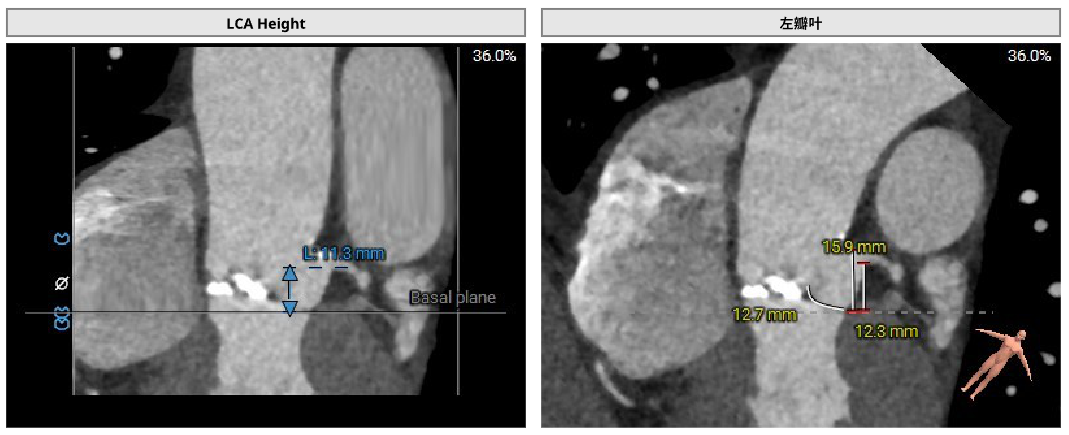

病例1:患者男性,70岁,三叶瓣。主动脉瓣重度狭窄,钙化集中于右冠窦、无冠窦,瓣环面积径23.3mm。左冠高度11.3mm,右冠高度16.1mm。外周入路可见钙化,内径尚可。

术中经右侧股动脉入路,使用19mm球囊预扩,顺利植入23# RENATUS®球扩式经导管主动脉瓣,瓣膜释放位置理想、形态及功能良好,无外周血管损伤,术后无瓣中及瓣周反流等并发症。